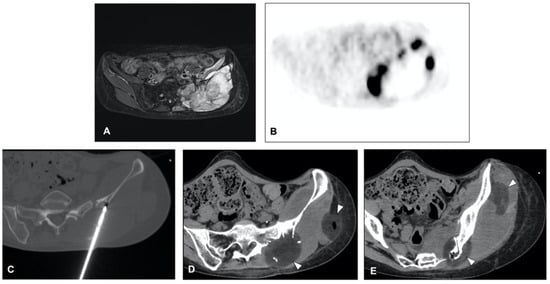

5. Desmoid Tumors

5.1. Cryoablation for Disease Control

5.2. Ablation Margin

- Kurtz, J.-E.; Buy, X.; Deschamps, F.; Sauleau, E.; Bouhamama, A.; Toulmonde, M.; Honoré, C.; Bertucci, F.; Brahmi, M.; Chevreau, C.; et al. CRYODESMO-O1: A prospective, open phase II study of cryoablation in desmoid tumour patients progressing after medical treatment. Eur. J. Cancer 2020, 143, 78–87. [Google Scholar] [CrossRef] [PubMed]

- Schmitz, J.J.; Schmit, G.D.; Atwell, T.D.; Callstrom, M.R.; Kurup, A.N.; Weisbrod, A.J.; Morris, J.M. Percutaneous Cryoablation of Extraabdominal Desmoid Tumors: A 10-Year Experience. Am. J. Roentgenol. 2016, 207, 190–195. [Google Scholar] [CrossRef]